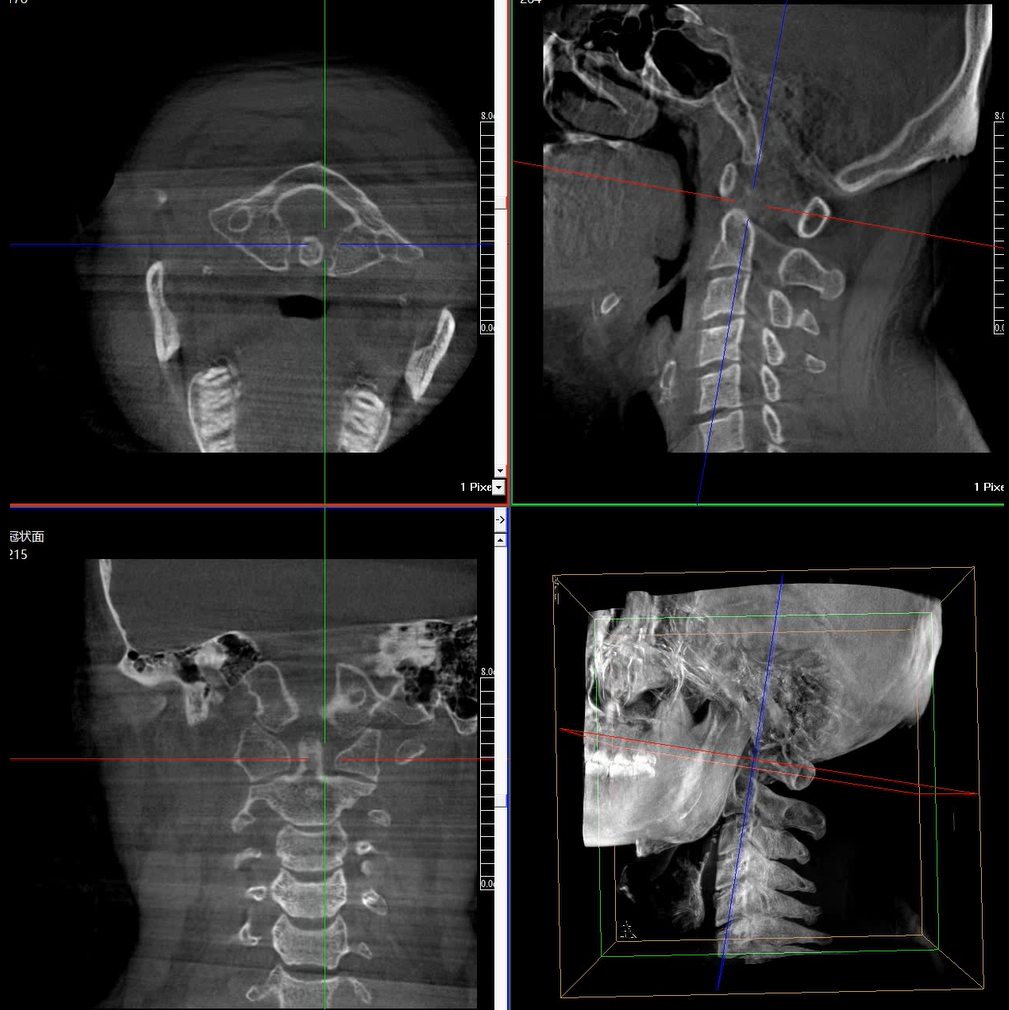

術(shù)中三維成像和橫斷面圖像提供多角度的手術(shù)診斷信息,輔助醫(yī)生進(jìn)行術(shù)中評(píng)估判斷,諸如骨折復(fù)位情況和內(nèi)植入螺釘?shù)某叽绾臀恢茫o助手術(shù)更好地完成。

提供更大的術(shù)中三維成像視野,采集更多圖像信息,可一次拍全全段頸椎、全段腰椎、七節(jié)胸椎、雙側(cè)骶髂關(guān)節(jié)、股骨頭及單側(cè)盆骨。